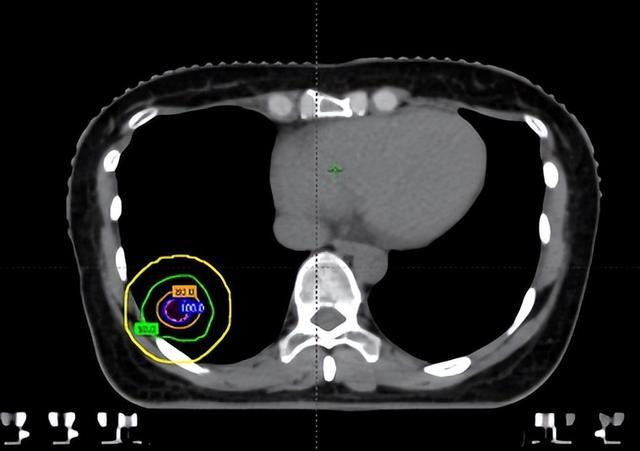

在维持前,团队通过四维CT对三个病灶进行精确定位,尤其是紧贴肋骨的阿谁病灶,连与肋骨之间极其微弱的裂缝齐被明晰标注出来。

随后参加最中枢的剂量狡计局势。胡英评释注解与李忠伟、雷大明物理师反复推演射澄清径和强度分散,把高剂量区域严格戒指在肿瘤鸿沟内,同期让剂量在极短距离内飞速下跌。不错清醒为,快乐飞艇在体内完成了一次“毫米级雕塑”:肿瘤被精确遮盖,而近在目前的肋骨却被保护在安全鸿沟内。